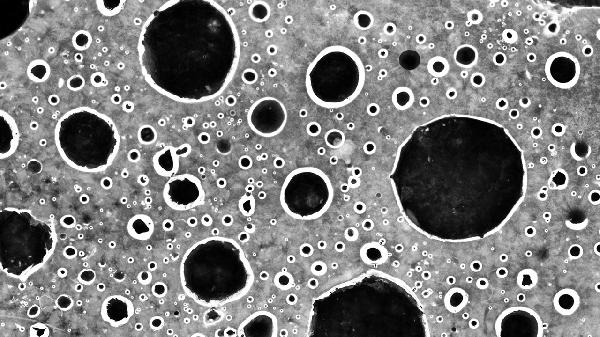

1、粪便常规检查是细菌性痢疾诊断的初步手段。正常情况下,粪便中白细胞数量较少,但在细菌性痢疾患者中,粪便中白细胞数量显著增加,尤其是中性粒细胞。中性粒细胞是人体免疫系统的重要组成部分,当肠道受到细菌感染时,中性粒细胞会迅速聚集到感染部位,吞噬和杀灭病原菌。粪便中发现大量中性粒细胞,提示可能存在细菌性痢疾。